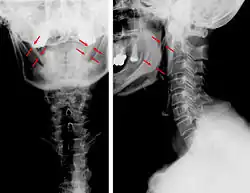

Zespół Eagle’a, stylalgia, zespół przedłużonego wyrostka rylcowatego[2] (ang. Eagle's syndrome, elongated styloid process syndrome) – stosunkowo rzadki zespół chorobowy, spowodowany nadmiernie długim wyrostkiem rylcowatym i (lub) zwapnieniem więzadła rylcowo-gnykowego. Objawia się napadowym, silnym, kłującym bólem w uchu, okolicy migdałka, dna jamy ustnej, bocznej części szyi lub kąta żuchwy. Ból może być wywołany przełykaniem, otwieraniem ust, obracaniem głowy, lub badaniem palpacyjnym gardła. Ból trwa kilka sekund lub minut, towarzyszy mu zwykle silny ślinotok. Leczenie jest głównie operacyjne. Opisywane są przypadki udanego leczenia zachowawczego[3]. Jednostkę chorobową opisał jako pierwszy amerykański otorynolaryngolog Watt Weems Eagle w 1937 roku[4][5][6][7]. Sklasyfikował on objawy wyszczególniając tzw. postać klasyczną występującą najczęściej po zabiegu usunięcia migdałków podniebiennych. Objawia się ona głównie izolowanym bólem w gardle w okolicy niszy po usuniętym migdałku, zaburzeniami połykania, bólem przy przełykaniu, uczuciem ciała obcego oraz wzmożonym ślinieniem. W niektórych przypadkach mogą pojawić się zaburzenia głosu. Dolegliwości te związane są z podrażnieniem V, IX i X nerwu czaszkowego poprzez ucisk tworzącej się ziarniny i (lub) blizny stymulujący wapnienie więzadła rylcowo-gnykowego. Druga postać to tzw. zespół tętnicy szyjnej związany z drażnieniem włókien współczulnych biegnących w ścianie tętnic szyjnych przez wydłużony wyrostek rylcowaty. Główne objawy to ból oka, zaburzenia widzenia, bóle połowicze głowy, bóle migrenowe, w skrajnych przypadkach omdlenia.